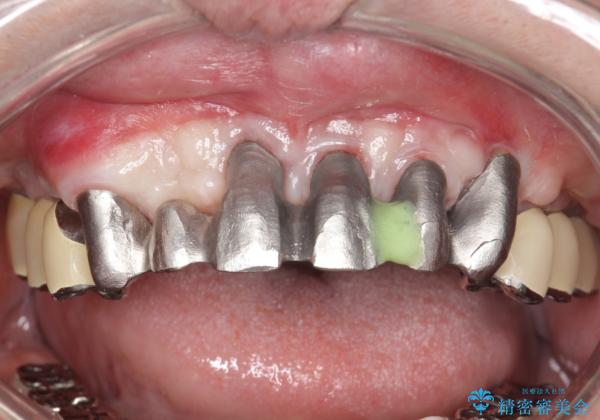

歯周病におかされた前歯の再建治療

- 歯周病により欠損が生じた歯槽骨、まずは再生治療をおこなう

→治癒後、確定外科を行い完全に歯周ポケットを除去し、最終的に歯周補綴をおこなう

かぶせ物の種類:PFM full bake